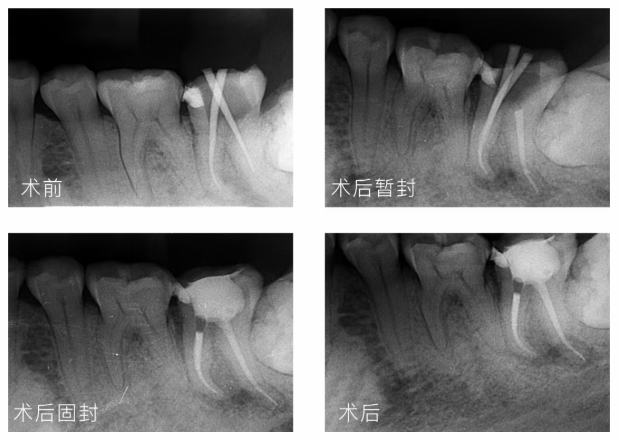

四、弯曲根管预备

根管预备到#25,即可结束根管塑形,轻松解决,让你用锉无忧

五、蓝晶灵根管治疗临床案例